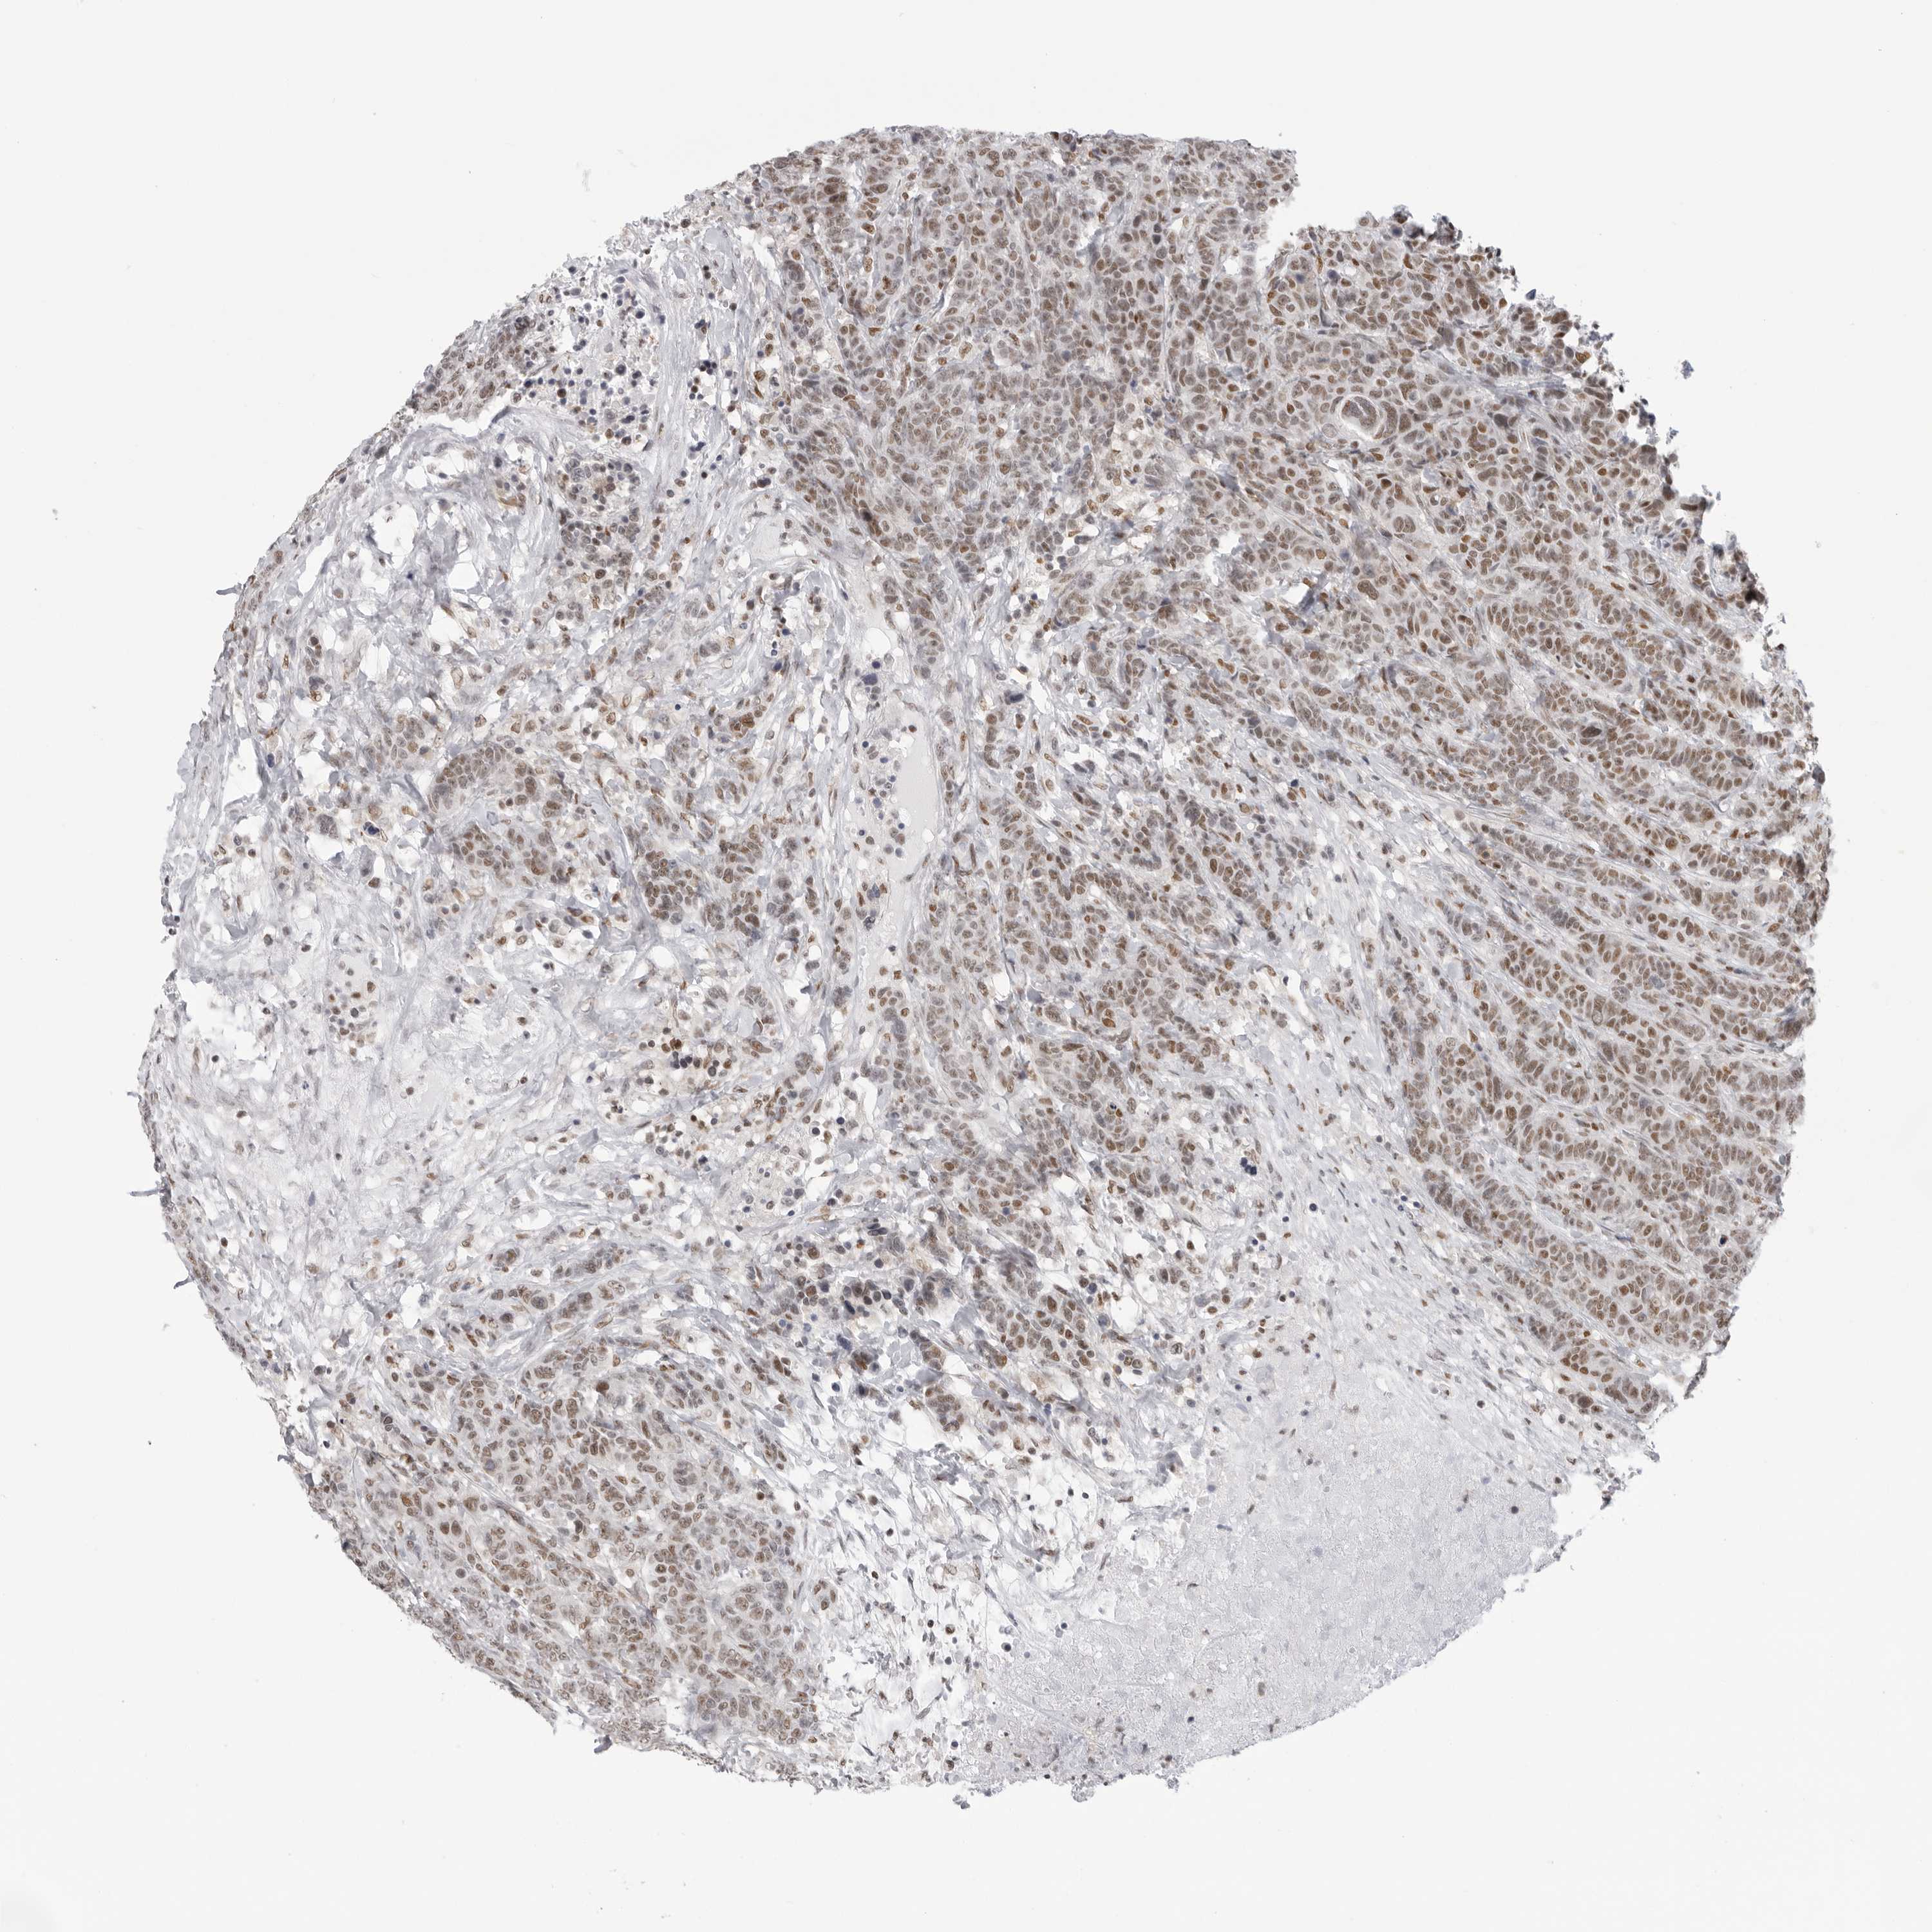

BRCA TCGA BRCA VALIDATION PROTEIN EXPRESSION

Breast cancer

Human cancer